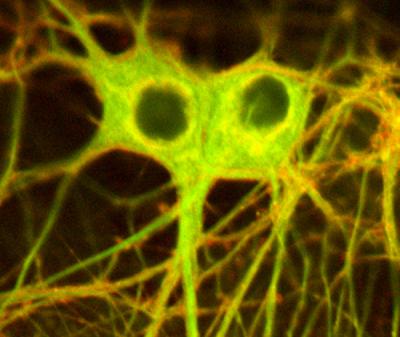

To confirm what was happening, scientists dosed two of a nerve cell's many different branches with NBD-steroid. When they shone a light on one of the branches, its readiness to respond decreased, while the readiness of the branch not exposed to light remained the same.